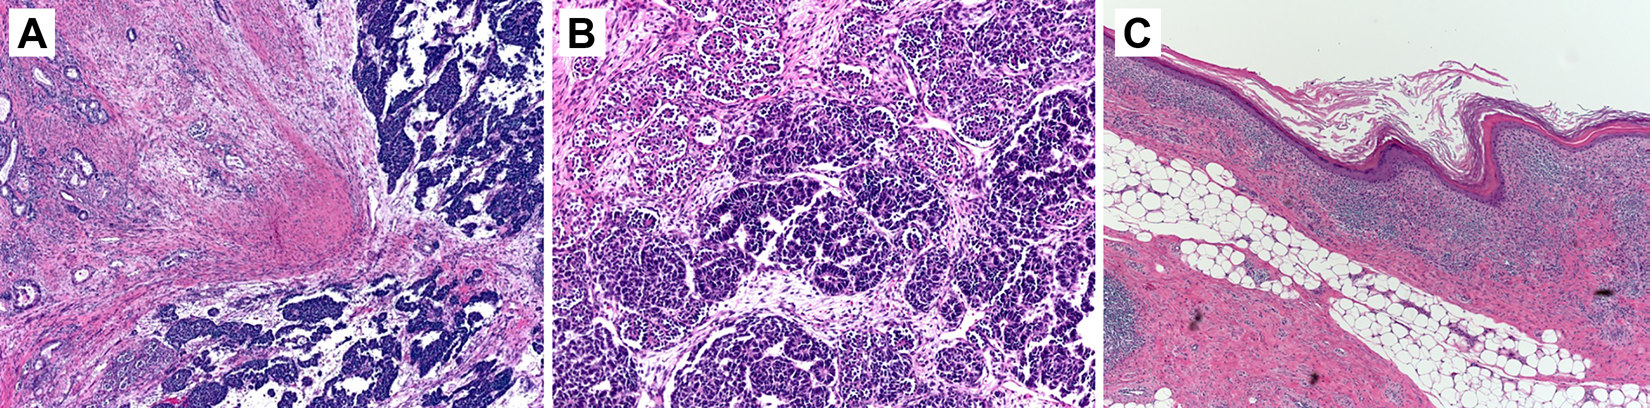

Microscopically, the tumor was predominantly nephroblastoma with intermixed areas of teratoma. The nephroblastoma component was composed of columnar epithelial cells with elongated hyperchromatic nuclei, nuclear molding, and high nuclear to cytoplasmic ratio arranged in tubules and nests with interspersed immature spindled stroma. Teratoma elements included tubular epithelium, primitive glomeruloid structures, cartilage, adipose tissue, and squamous epithelium (Figure 2).

Histologic evaluation using hematoxylin-eosin staining demonstrated (A) teratoma (left side) with secondary somatic malignant neoplasm in the form of nephroblastoma (right side) (low magnification); (B) nephroblastoma with adjacent primitive glomeruloid structures and nephroblastoma composed of columnar epithelial cells with elongated, hyperchromatic nuclei arranged in tubules and nests (high magnification); and (C) teratoma including squamous epithelium and adipose tissue (low magnification).